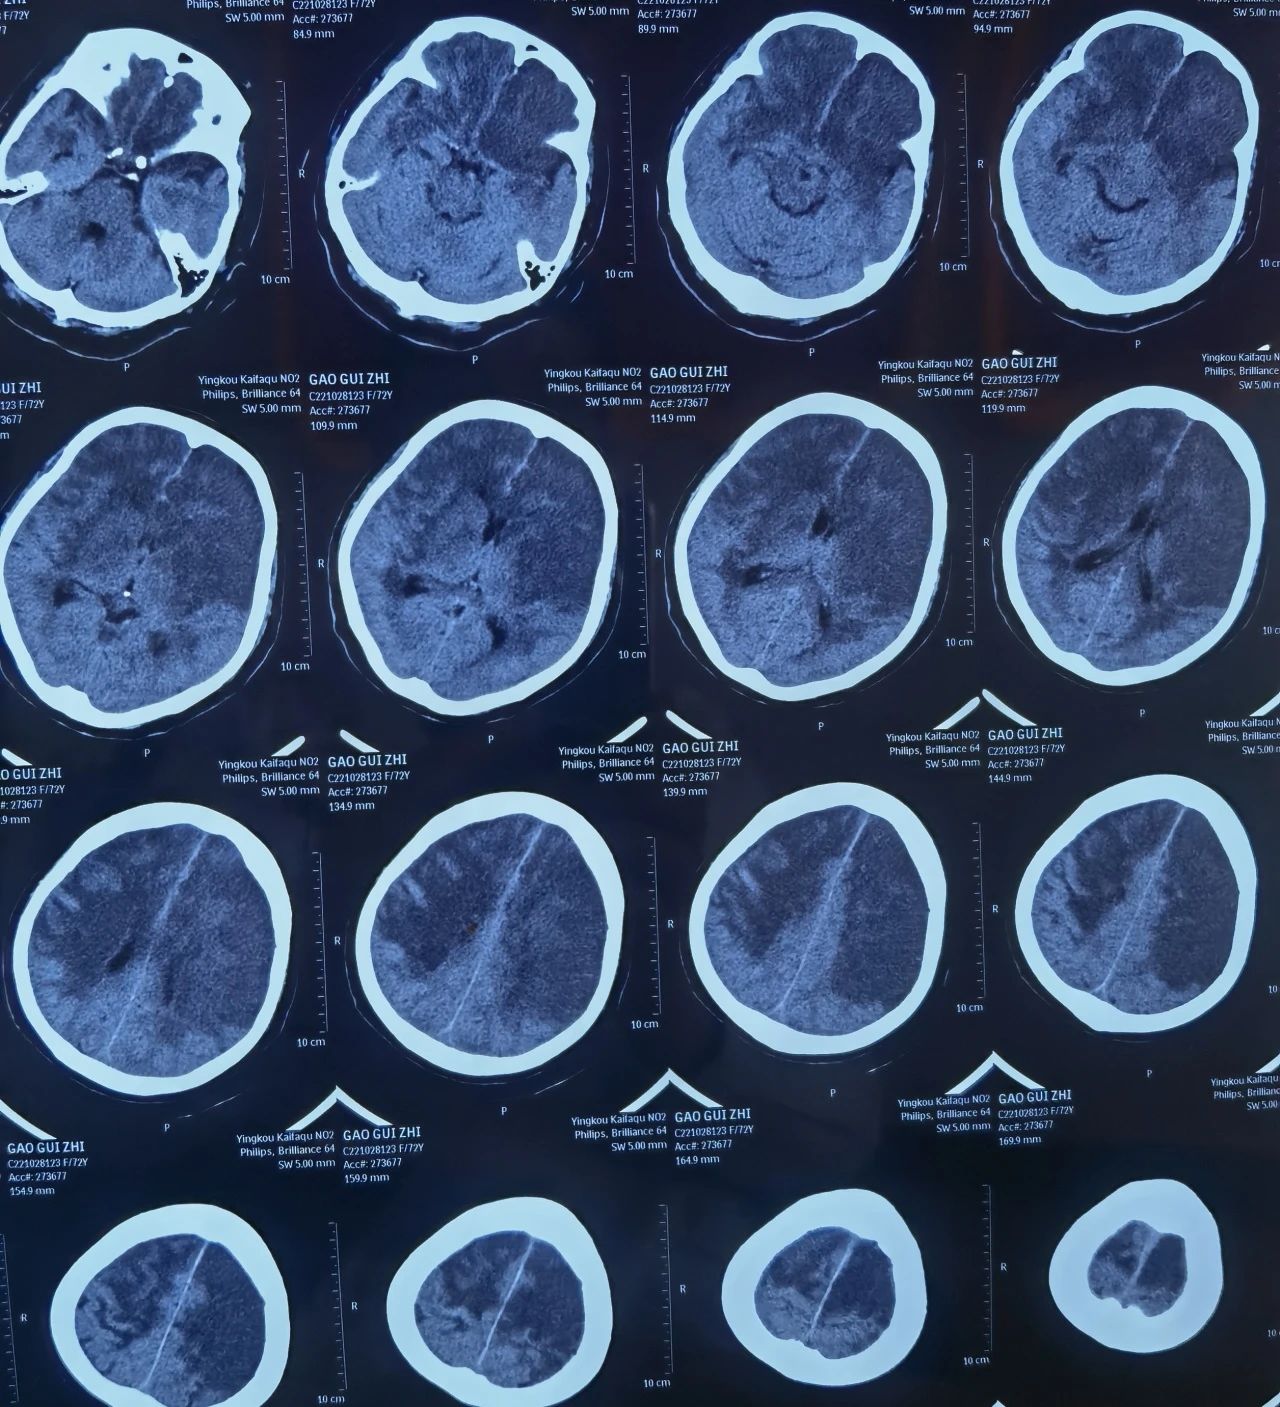

老年病科王珺主任接诊时,高奶奶已经中度昏迷,血压180/108mmHg,影像报告提示右侧大面积脑梗塞,极容易出现脑疝,若不及时救治可直接危及生命。

(入院时,右侧大脑半球约三分之二大片状梗死灶,大脑中线向左侧移位)

病情危急,王珺主任立即给予系统治疗,缓解相应症状,使患者脱离了生命危险。但由于患者本就患有动脉血管狭窄且年龄较大,基础性疾病多,入院第八天突发昏厥,同时合并继发癫痫,CT显示由单侧脑梗塞发展为双侧大脑干球大面积梗死,随时可能引起心跳、呼吸骤停。

(入院8天后,大脑半球约三分之二出现大片状梗死灶)